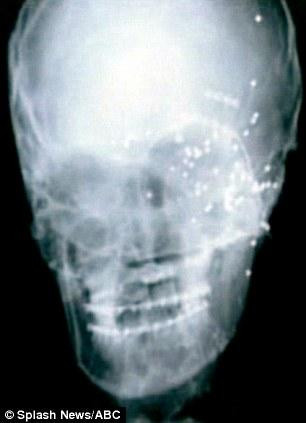

ABD’de 11 yıl önce şakalaşma sırasında bir arkadaşının boş sandığı tüfeğin tetiğine basmasıyla yüzü parçalanan, gözleri, burnu ve elmacık kemik leri yok olmasına karşın mucize eseri kurtu lan Chrissy Steltz, doktorların son teknolojiyi kullanarak geliştirdiği protez maskeyle yeni yüzüne kavuştu.

Geçen yıl bir erkek çocuk dünyaya getiren Steltz’ in kazadan önceki fotoğraflarını inceleyen doktorlar, genç kadının yüzüne uygun bir protez maske geliştirdi.